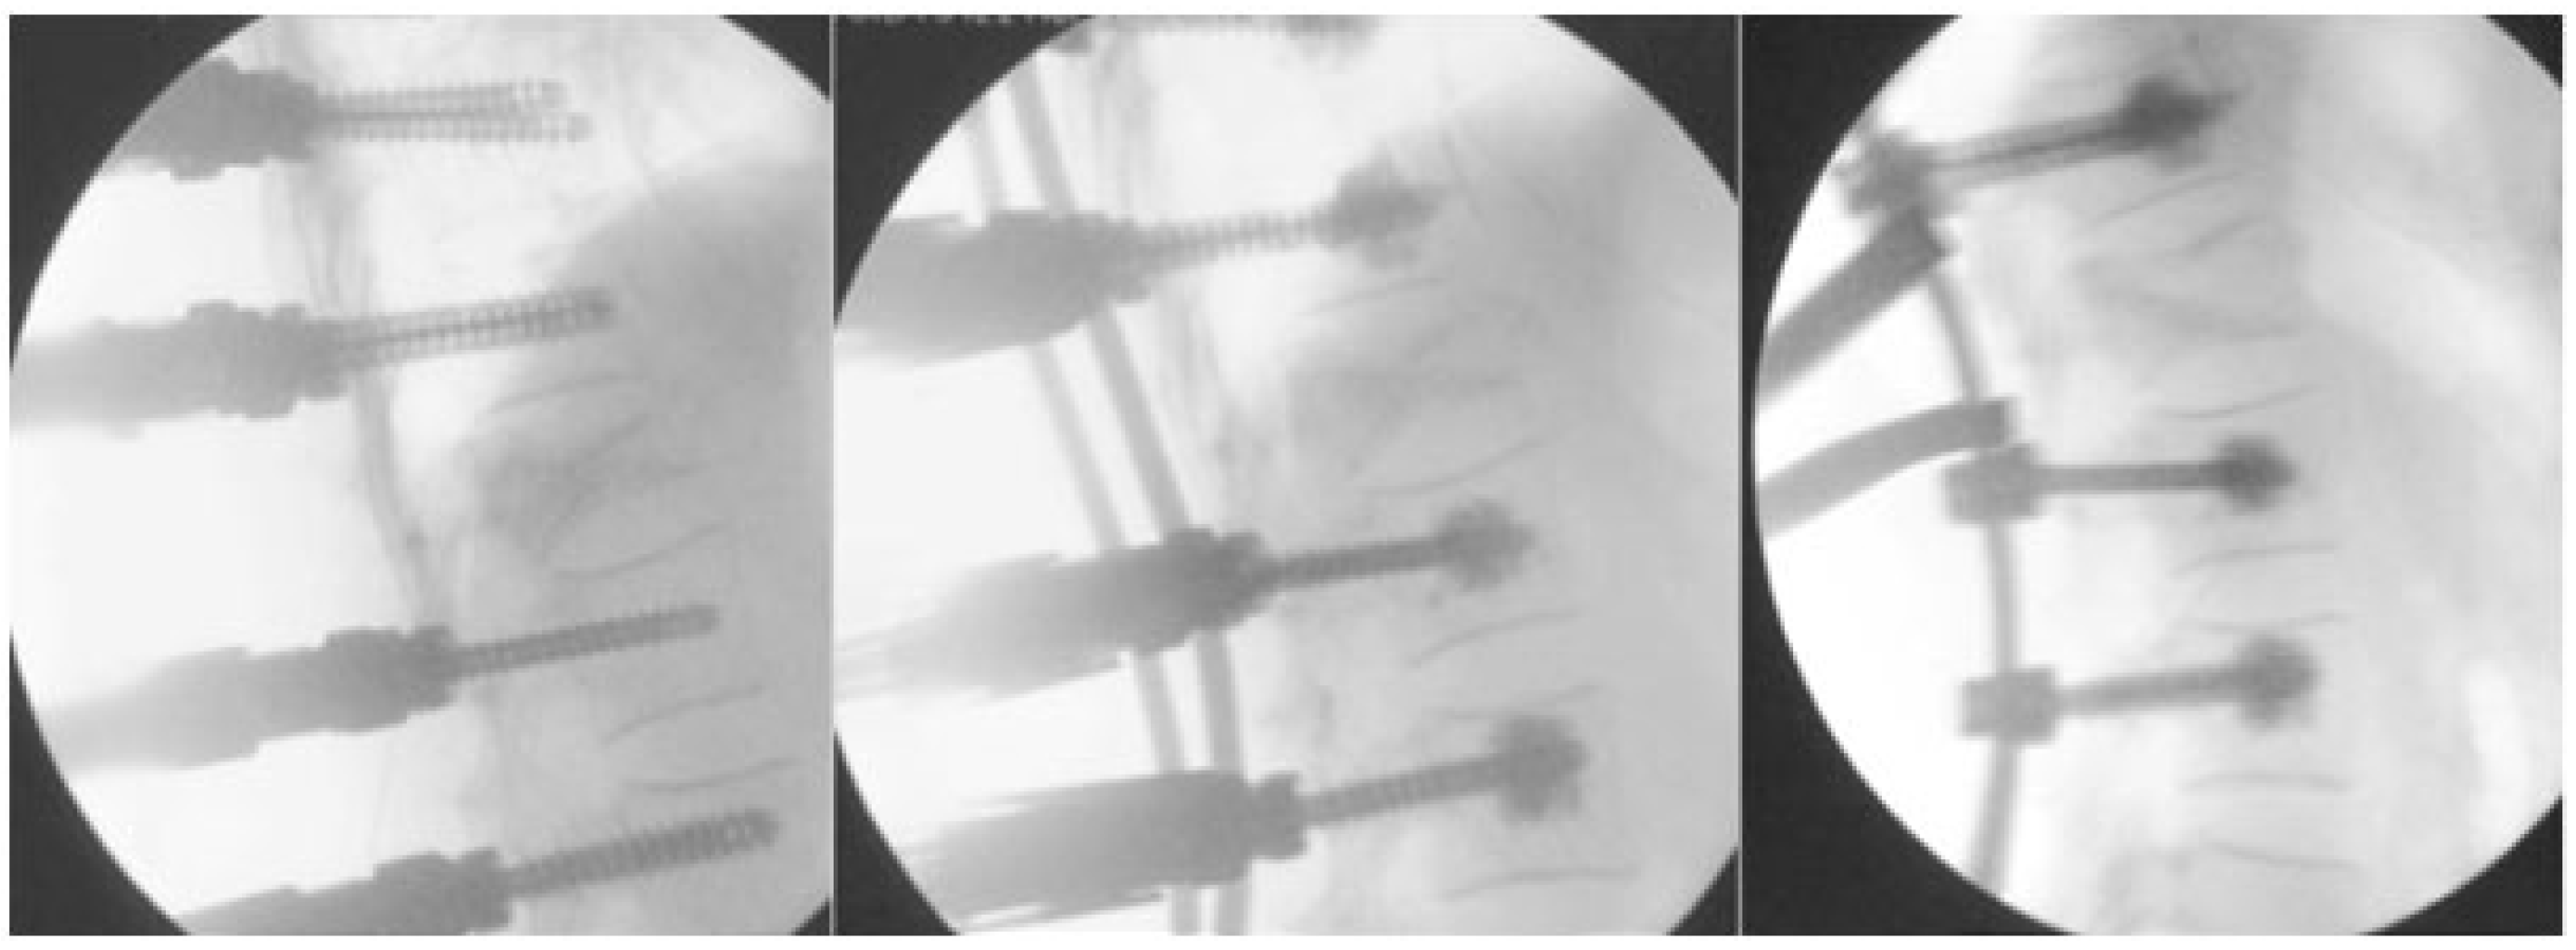

- Optimally reducing pathological fracture. The reduction by osteosynthesis will then allow for optimal vertebro/kyphoplasty.